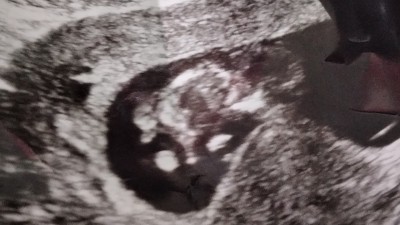

cinsiyet anliyan canimlar

cinsiyet tahmini

Gebelik haftası

12

Erkek gibi geldi bana bir minik çıkıntı var gibi. Sağlıkla gelsin :)

çok sagol bebegim bende erkek içimden geciyo ama TSK ederm bitanem